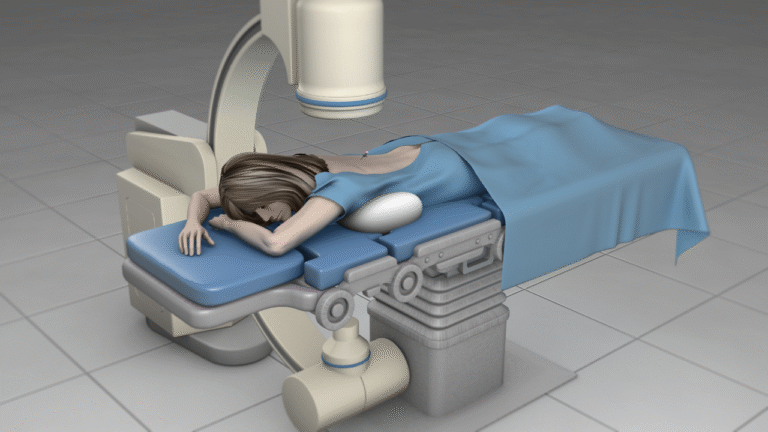

- Procedure mini-invasive

- Neuromodulazione